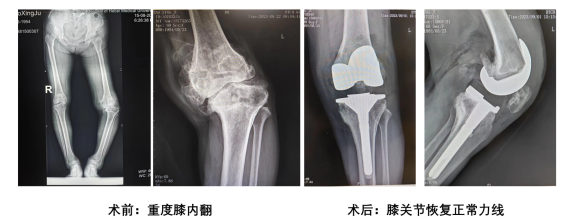

3. 个性化微创全膝置换术:是全球率先开展的最微创最适配原生关节的个性化全膝置换术,根据患者自己膝关节的多模态建模,个性化设计3D打印定制全膝置换人工膝关节。个性化人工关节的力学强度、耐磨性和耐腐蚀性均优于标准人工膝关节,重金属离子析出也远少于标准人工关节。术中假体的位置和下肢矫正力线,在术前数字化智慧术前规划中就已经设计好,手术中使用专为患者自己设计的手术导板,可以轻松实现假体位置和矫正的力线的准确性;术中假体实现95~98%以上的切骨面覆盖,使术中和术后出血显著减少,手术时间还因基于多模态影像建模设计的手术导板的使用减少一半。术后,膝关节的功能和运动更接近天生关节,术后康复速度也明显加快。

15. 膝关节骨关节炎的分级诊断和台阶治疗:在膝关节专科,将膝关节骨关节炎从轻度到重度(重度又叫终末期)分成Ⅰ度~Ⅳ度(终末期是Ⅳ度),对不同程度的骨关节炎分成五个台阶治疗,分别是康复体能训练(第一台阶)、药物治疗和肌力练习(第二台阶)、关节镜手术(第三台阶)、截骨保膝(第四台阶)和部分置换和全膝置换治疗(第五台阶)。不同轻重的骨关节炎诊断和不同台阶的治疗之间,界限分明,有效避免了治疗不充分或治疗过度的全球难题,让不同严重程度的膝关节骨关节炎患者都可以获得收益最大化的治疗。